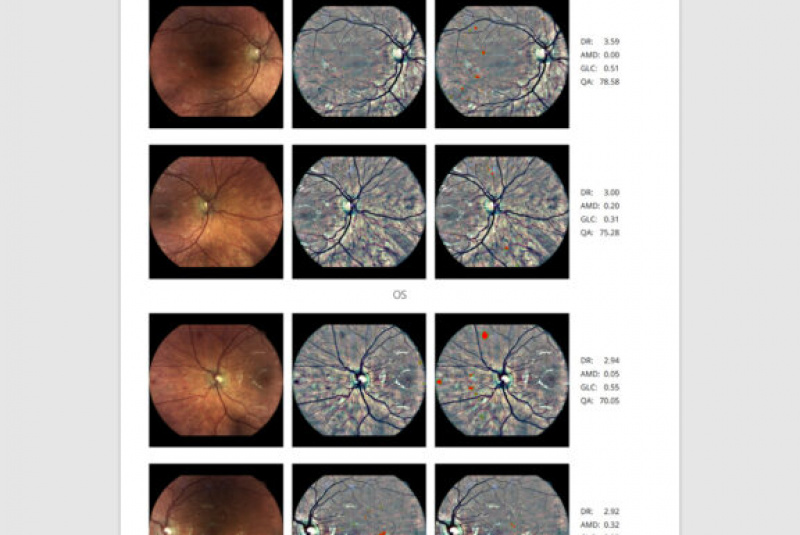

AI (umelá inteligencia) okamžite rozpozná práznaky diabetickej retinopatie a klasifikuje výsledky podľa závažnosti na základe medzinárodných klasifikácií. Získate prehľad s hodnotením závažnosti záchytu, kde po analýze snímok zachytených kamerou iCare DRS Plus je automaticky generovaný report o pacientovi so stupnicou závažnosti pre diabetickú retinopatiu na základe medzinárodných štandardov (ICDR, AREDS).

Fundus kamera iCare DRSplus urobí celkovo 4 vysoko kvalitné True Color snímky (dve z pravého a dve z ľavého oka), ktoré sa automaticky ukladajú na cloud a posielajú sa na spracovanie AI - umelej inteligencii. Report je dostupný ihneď a ten je možné prekonzultovať s pacientom počas tej istej návštevy u lekára.

Software RetCAD

- schopnosť zhodnotiť tak takmer 100 % snímkov

- Výsledok na škále 0-4 podľa ICDR

- International Clinical Diabetic Retinopathy

(medzinárodná klinická škála závažnosti diabetickej retinopatie) - Výsledok generovaný na základe 2 snímkov z každého oka

(centrálne a nazálne)

Medzinárodný oftalmologický štandard vyžaduje

výsledok podľa min. 2 snímkov z každého oka.